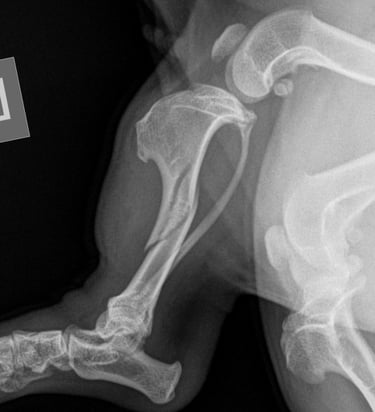

Tibia fracture - Mini Dachshund, 2y, female

This small and sweet 5.4 kg female patient sustained a lameness after playing in the garden allotment. Orthogonal radiographs revealed a surgical, long oblique spiral mid-diaphyseal fracture of the left tibia (Fig. 1 and 2).

Fig. 2